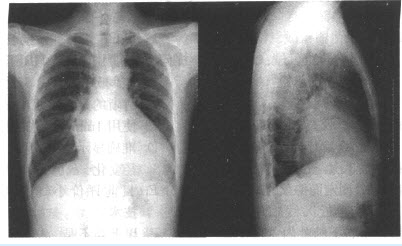

患儿,男,2岁。乏力、多汗,活动后气促1年余。查体:胸骨左缘第2~3肋间可闻及收缩期吹风样杂音。X线胸片如下图所示。

(多选题)对上图所见描述正确的是()

A:右房增大

B:左房增大

C:右室增大

D:左室增大

E:心腰突出

F:左房左室大

(单选题)根据上图,最可能的诊断是()

A:室间隔缺损

B:房间隔缺损

C:法洛四联症

D:主动脉导管未闭

E:先天性肺动脉狭窄

F:动脉导管未闭